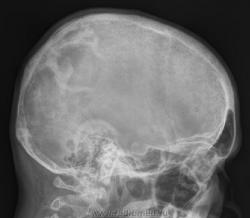

Миеломная нет (если иметь ввиду солитарную миелому); есть просветление, есть склероз по периферии,есть елементы вздутия, тенеобразование как бы состоит из двух частей - может быть эозинофильная гранулема?

Жалко что не успел к разбору данного случая... Не хочу хвастаться, но мне сразу в голову пришел гиперпаратиреоидизм... Немного конечно смутил дефект с склерозом, но в передней части снимка черепа, есть типичные изменения, которые кстати не были упомянуты выше, я имею в виду зернистость костной структуры, обозначенной в английской литературе как salt-and-pepper, по русски - признак "соль-с-перцем". Типичный признак при гиперпаратиреоидизме. Вот небольшая статья по теме:

Salt and pepper skull

Figure 5: Salt and pepper skull

Brown tumors are more common in patients with primary hyperparathyroidism, however, due to the increased prevalence of secondary hyperparathyroidism, there are more brown tumors from secondary hyperparathyroidism than form primary hyperparathyroidism.It is difficult to differentiate a Brown Tumor from a giant cell tumor or fibrous dysplasia; however, other signs of hyperparathyroidism should be present.

ГИПЕРПАРАТИРЕОИДНАЯ ОСТЕОДИСТРОФИЯ.